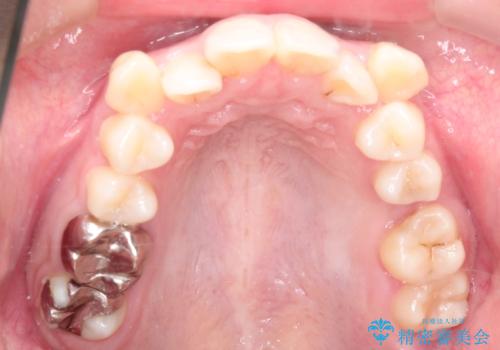

- 患者様は、下顎両側の第1大臼歯(6番)と右上6番の欠損を主訴に来院されました。

通常であればインプラントによる補綴が第一選択となる症例でしたが、患者様ご自身がインプラントを希望されなかったため、矯正治療によって欠損部の閉鎖を図る方針としました。

同時に、親知らず(智歯)の萌出や位置も考慮し、咬合全体のバランスを改善する矯正治療計画を立案しました。

ワイヤー矯正を用いて、欠損部の閉鎖を目的とした後方からの歯の挺出・移動を行いました。

特に、親知らずを活用し、奥歯の噛み合わせを構築することに重点を置きました。

最終的には予定通りインプラントを使用せずに欠損部を閉鎖し、咬合も安定させることができました。